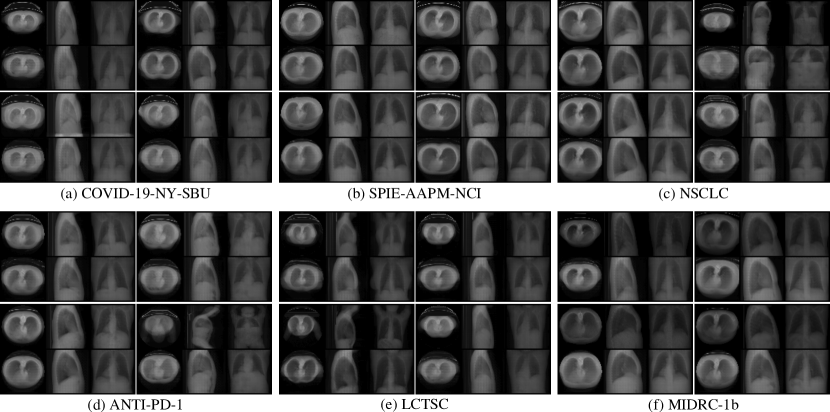

In Table 2 we compare our approach to paired alternative methods in terms of quality of the 3D outputs for both in- and out-of-distribution inputs. Despite variations in datasets originating from different imaging systems, resolutions, and patients’ health conditions, our model demonstrates superior performance across all metrics and maintains consistency across all out-of-distribution datasets. Refer to Figures 5 and 9 for qualitative results.

Refer to caption

Figure 5: CT projections from generated 3D volumes on various out-of-distribution lung datasets. Model weights were selected from iteration 5,000 on the LIDC-IDRI dataset [1]. GT projections are displayed in odd rows, while our model’s outputs are shown in even rows.